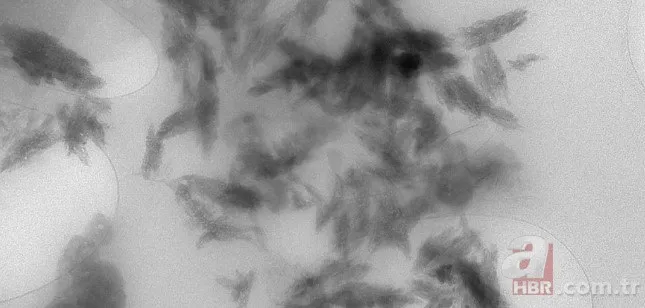

Bilim insanları, taramalı elektron mikroskobu (SEM) ve enerji dağılımlı X-ışını spektrometrisi (EDS) ile yaptıkları incelemelerde, beyindeki partiküllerin karbon bazlı olduğunu doğruladı.

PLASTİKLER CAM KIRIĞI GİBİ

Karaciğer ve böbrekteki MNP bileşen miktarının benzer oranlarda olduğunu saptayan araştırmacılar, beyindeki plastiklerin "mikroskobik boyutlarda cam kırığı" şeklinde gözlemlendiğini belirtti.